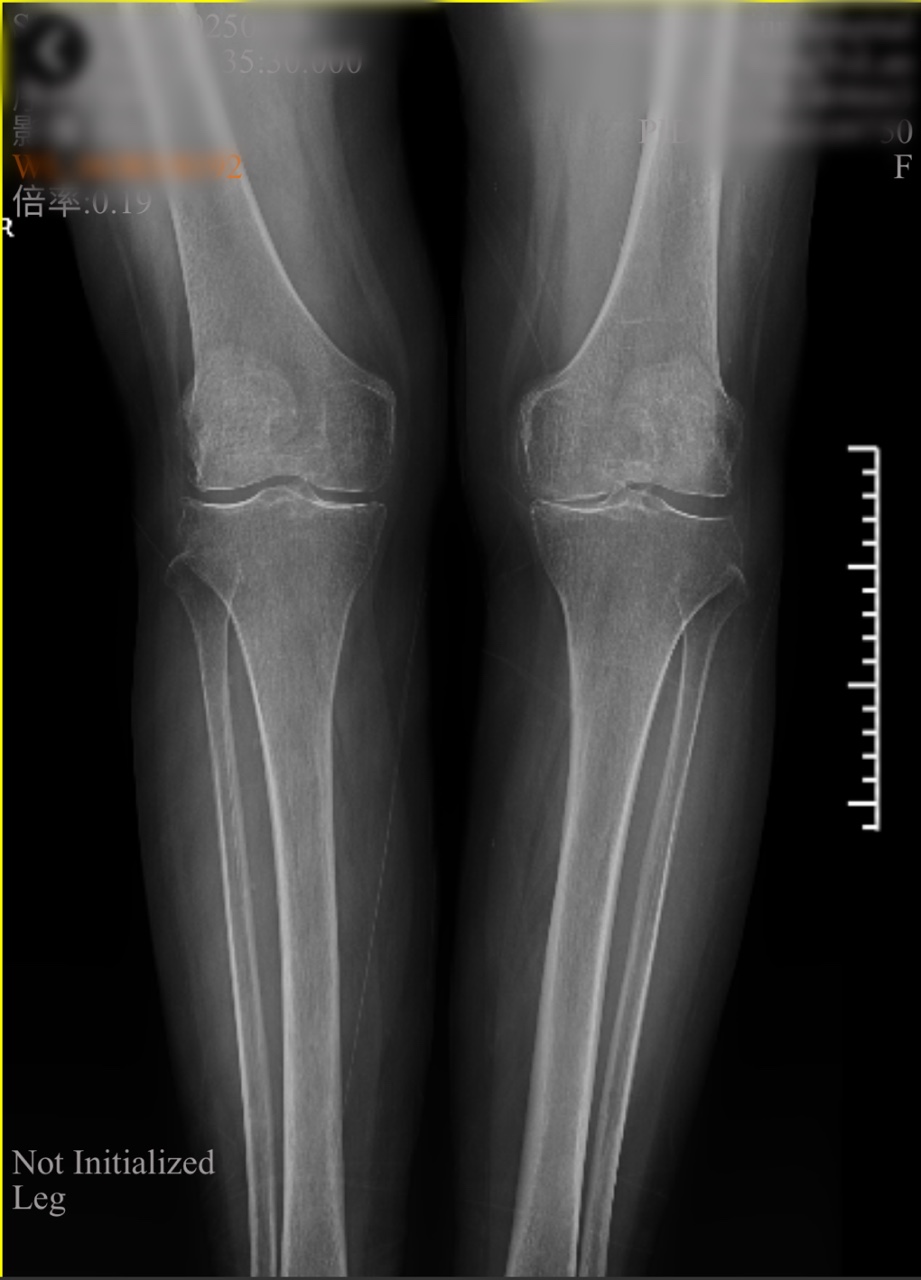

檢查室里,魏海清主任帶領(lǐng)團(tuán)隊(duì)為李阿姨做了詳細(xì)查體。“膝蓋內(nèi)翻畸形,軟骨剝脫,關(guān)節(jié)間隙明顯變窄......”影像學(xué)檢查證實(shí)了醫(yī)生的判斷:左膝關(guān)節(jié)骨質(zhì)增生嚴(yán)重,關(guān)節(jié)面硬化,屈伸活動(dòng)已嚴(yán)重受限。